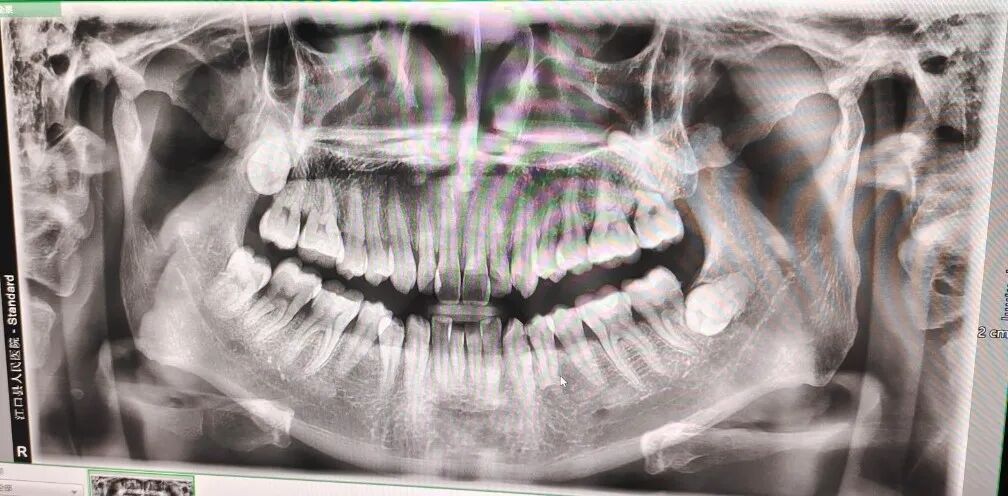

CBCT是目前国际最先进的口腔科专用CT,在业界被誉为神奇的"慧眼",具有扫描快、范围大、精度高、应用广、放射剂量极低的特点。可以通过其强大的处理软件功能以及面部匹配技术迅速形成清晰逼真的三维图像,在智齿拔除、牙种植测量、多生牙定位、颞下颌关节疾病、颌骨三维重建、根管治疗评估、正畸设计等方面提供精准的诊断与治疗依据。

5.8类拍摄模式:成人全景、儿童全景、前齿拍摄、左侧拍摄、右侧拍摄、TMJ张口、TMJ闭口、上颌窦。